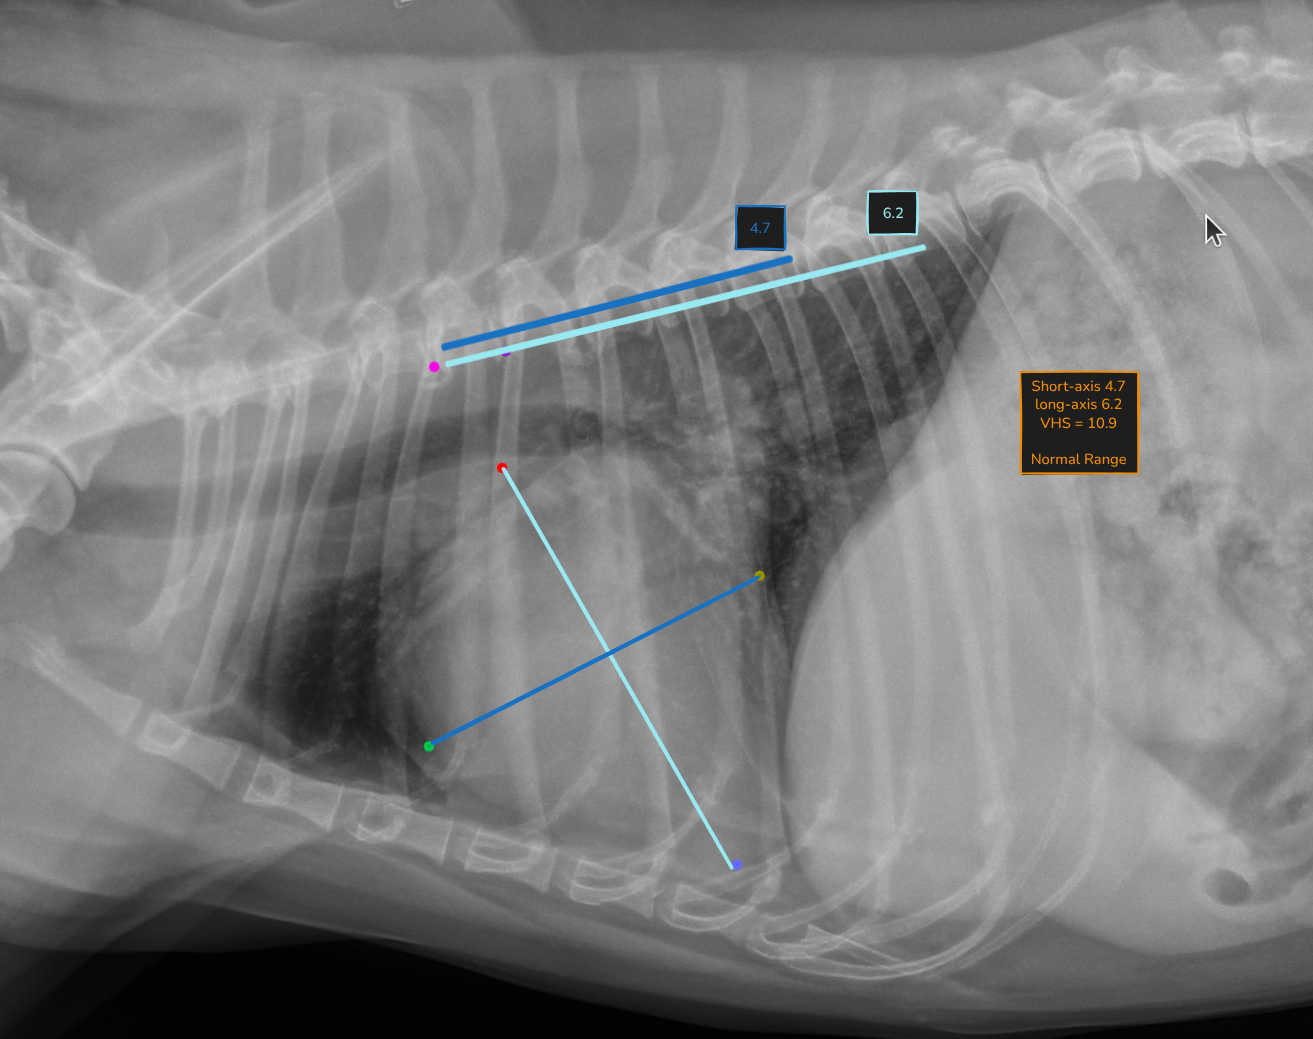

Automated VHS calculation

Vertebral Heart Score is calculated automatically on every lateral thoracic radiograph. The measurement is overlaid directly on the image with vertebral reference lines, so you can verify it at a glance.

No more manual measurement. No more variability between reads. Just a consistent, repeatable number ready for your interpretation.